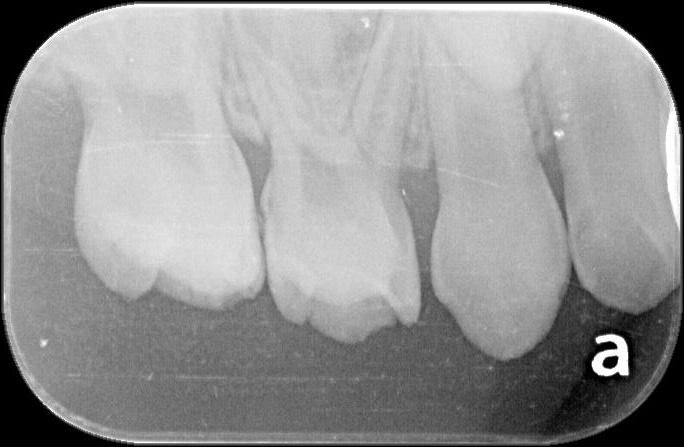

4살아이 눈으로도 시급한게 아래2개 위에 2개정도입니다.그런데 10개나 치료해야되고 8개를 크라운을 씌워야 된다고 하는데요 사진상에도 그런가요?

x-ray 사진상에서 치아와 치아 사이 충치가 있습니다. 어금니 치아와 치아 사이 충치는 눈에 잘 안보이지만 안으로 많이 진행된 경우가 많습니다.

치아 사이에 충치가 많이 진행되 상태 같습니다. 치료를 받아보시는게 좋을것같습니다. 신경치료 가능성도 있어 보입니다.

사진에서는 올려주신 치아 대부분에 충치가 보입니다. 정확한 갯수는 알 수 없으나 다수 치료해야합니다.

1. 유치는 충치가 있다고 반드시 치료해야 하는 건 아니고 곧 빠질 유치의 경우 그냥 두기도 합니다. 다만, 만4세면 앞으로 유치가 빠지기 시작하기까지 최소 2년정도 남았으므로 충치 있으면 치료해야 합니다.